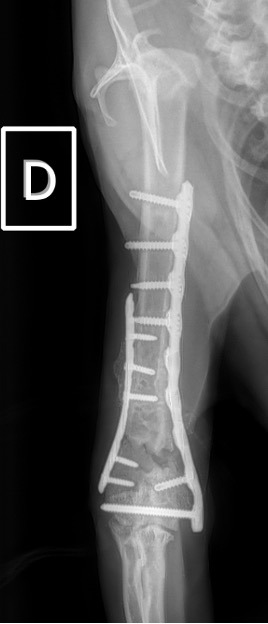

Notre préférence va vers le placement de deux plaques humérales : une médiale de la plus grande taille possible et l’autre latérale, généralement d’une taille inférieure à la première. Dans l’exemple 1 (chat européen), une plaque de 2 mm est utilisée médialement et une plaque de 1,5 mm latéralement. Dans l’exemple 2 (chien Malinois), une plaque de 3,5 mm est utilisée médialement et une plaque de 2,7 mm latéralement.

Figure 2 : Post-Op Immédiat

Figure 3 : Post-Op 1 Mois

Figure 3 : Post-Op 2 Mois

Exemple 2 :

Figure 4 : Pré-Op